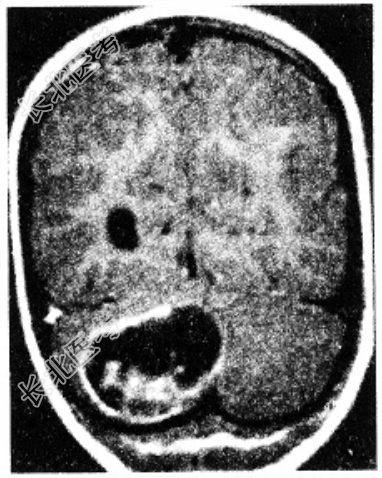

男性患者,39岁。头痛、步态不稳3个月。查体:神清,双侧视盘水肿,右侧轮替动作不能。周围血象红细胞增多,B超发现右肾有一囊性肿物,头颅CT发现右小脑半球囊性占位性病变(如图所示)。